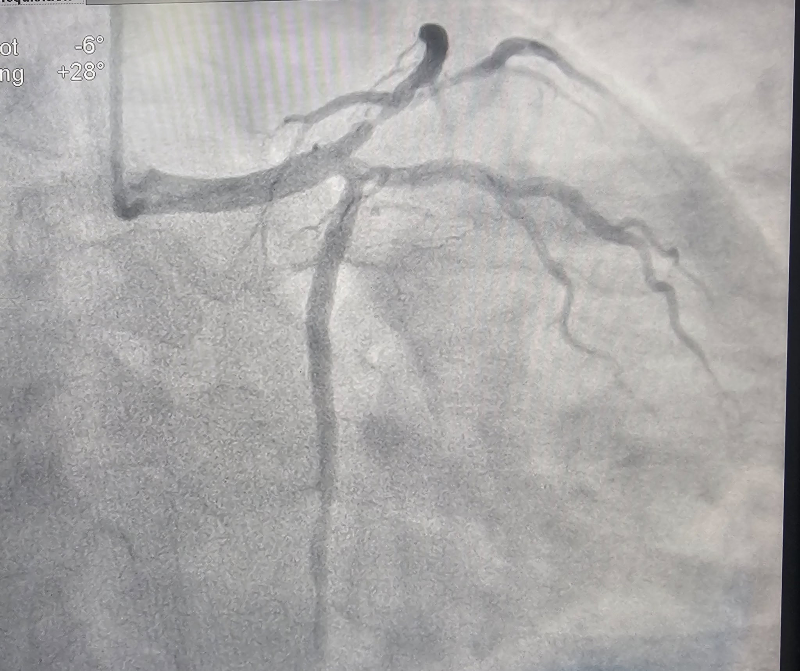

Các bác sĩ Khoa Tim mạch – Bệnh viện Bãi Cháy vừa can thiệp thành công cho bệnh nhân nam 34 tuổi bị nhồi máu cơ tim cấp. Kết quả chụp mạch vành cho thấy bệnh nhân hẹp 90% động mạch liên thất trước (LAD) và nhánh chéo 1 (Diag1). Người bệnh được xử trí kịp thời bằng kỹ thuật can thiệp đặt stent chỗ chia đôi (Mini-Crush), tái thông dòng chảy mạch vành, giúp bảo toàn chức năng tim.

Thạc sĩ, bác sĩ Đinh Danh Trình, Trưởng khoa Tim mạch, Bệnh viện Bãi Cháy cùng ê kíp đang tiến hành chụp và can thiệp đặt stent mạch vành cho bệnh nhân.

Hình ảnh: trước và sau khi can thiệp